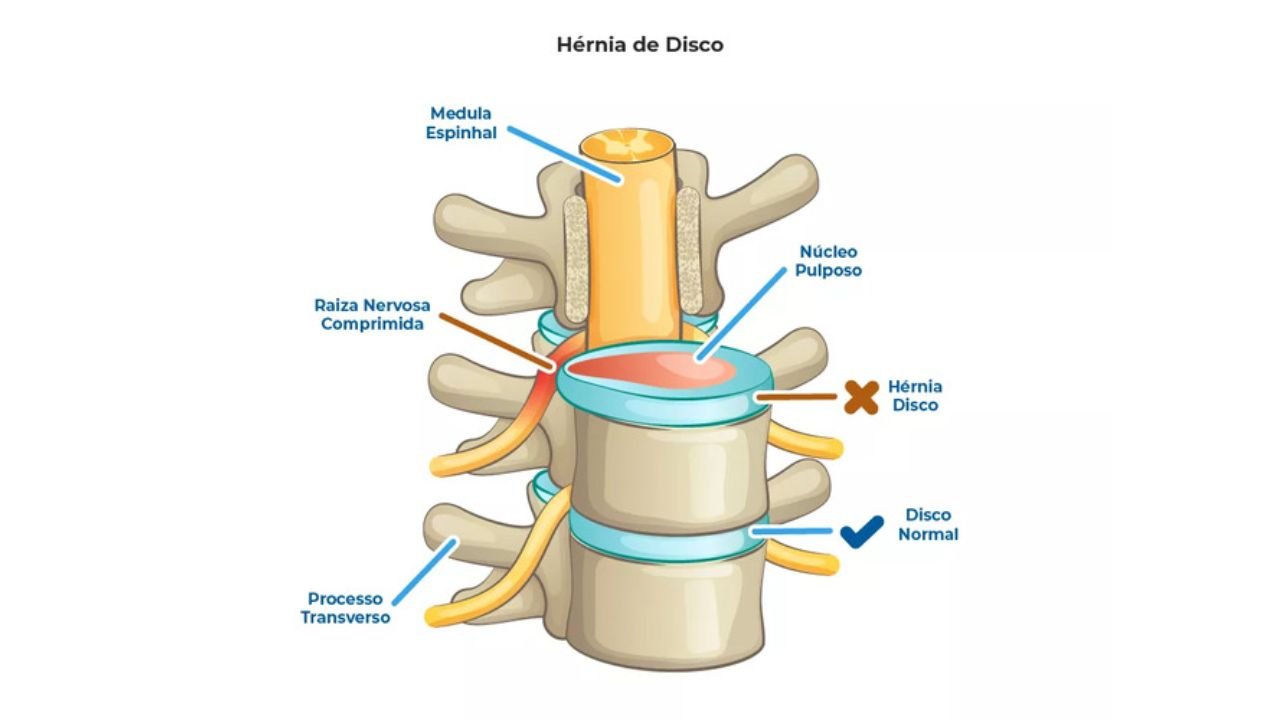

Receber o diagnóstico de uma hérnia de disco pode ser intimidante, muitas vezes associado à imagem de uma cirurgia de

Receber o diagnóstico de uma hérnia de disco pode ser intimidante, muitas vezes associado à imagem de uma cirurgia de

Receber o diagnóstico de uma hérnia de disco pode ser intimidante, muitas vezes associado à imagem de uma cirurgia de